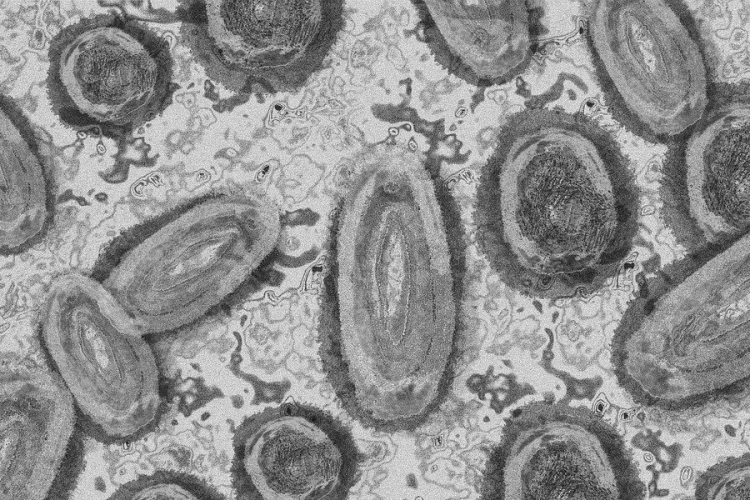

Tovább nőtt a majomhimlő-fertőzöttek száma Magyarországon

Újabb kilenc, 23-50 éves férfinél igazolták a majomhimlő-fertőzést Magyarországon, ezzel 42-re nőtt a fertőzöttek száma - közölte a Nemzeti Népegészségügyi Központ (NNK) csütörtökön az MTI-vel.